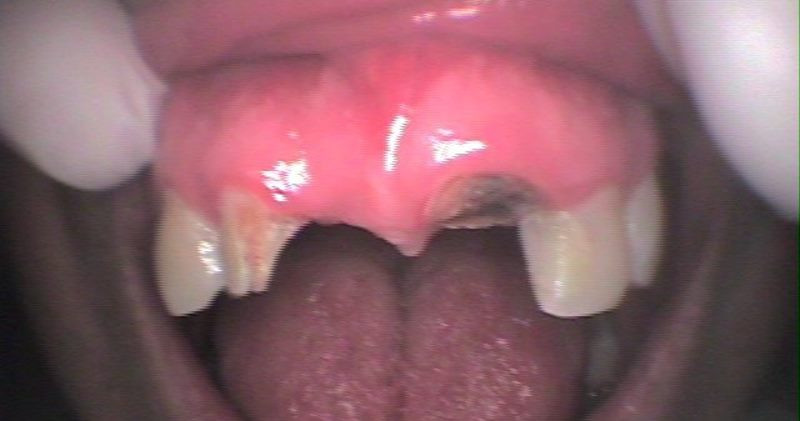

Vista oclusal inicial

Vista oclusal previa impresión